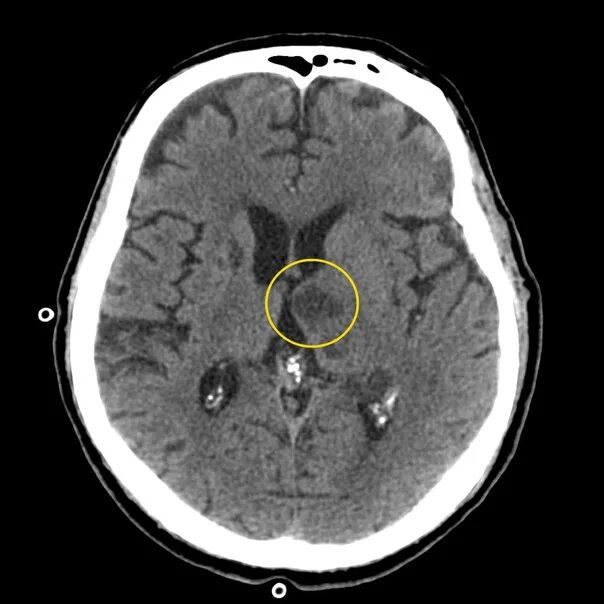

Киста базальных ядер слева